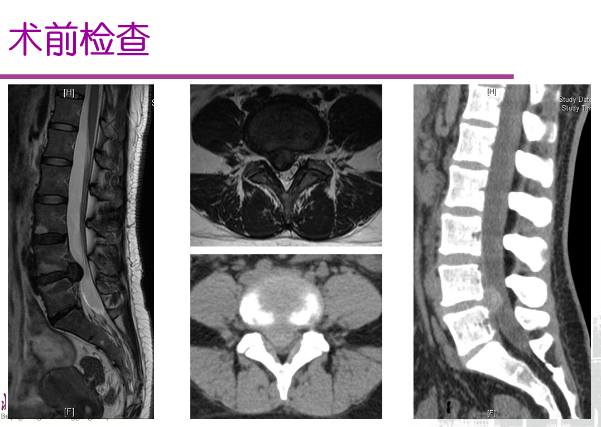

图4 孙振兴主治医师展示的微通道下腰椎间盘探查术